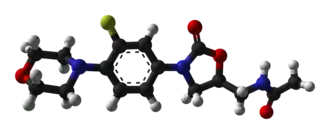

При физиологическом рН, линезолид существует в незаряженном состоянии. Он умеренно растворим в воде (приблизительно 3 мг/мл), с log Р 0,55.[26]

Оксазолидиноны являются ингибиторами синтеза белка: они останавливают рост и размножение бактерий, нарушая трансляцию белков на рибосомах. Хотя механизм действия полностью не понятен,[86] линезолид, вероятно, действует на первом этапе синтеза белков — инициации — в отличие от большинства других ингибиторов синтеза белка, которые препятствуют элонгации.[81][87]

Препарат делает это путём предотвращения образования инициирующего комплекса, состоящего из 30S и 50S субъединиц рибосомы, тРНК и мРНК. Линезолид связывается с 23S частью 50S субъединицы (центр действия пептидилтрансферазы),[88] рядом с областью связывания хлорамфеникола, линкомицина и других антибиотиков. В связи с этим уникальным механизмом действия, перекрёстная резистентность между линезолидом и другими ингибиторами синтеза белка возникает очень редко или вовсе отсутствует.[5][26]

В 2008 году кристаллическая структура линезолида, связанная с 50S субъединицей рибосомы архея Haloarcula marismortui, была выделена группой учёных из Йельского университета и хранится в Protein Data Bank.[89] Другая группа учёных в 2008 году определила структура линезолида, связанного с 50S субъединицей Deinococcus radiodurans. Авторы предложили уточнённую модель механизма действия оксазолидинонов, установив, что линезолид занимает А область 50S рибосомной субъединицы, вызывая конформационные изменения, что предотвращает попадание тРНК и, в итоге, заставляя тРНК отделиться от рибосомы.[90]